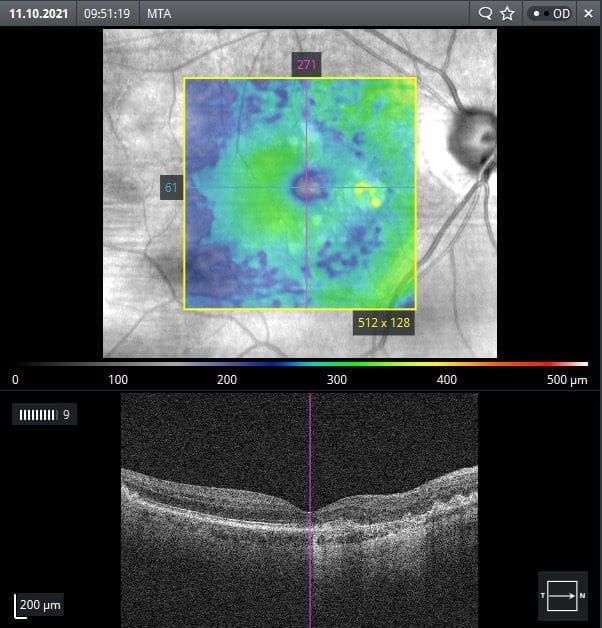

Die Intervalle der Kontrolluntersuchungen und die Therapie erfolgen in Abhängigkeit der Ausprägung pathologischer Veränderungen: Liegen keine oder milde Veränderungen vor, erfolgt eine jährliche Kontrolle. Bei sichtbaren Veränderungen – vor allem bei ödematösen Veränderungen im Bereich der Fovea – sind eine zeitnahe ärztliche Vorstellung (so auch beim Patienten aus Abbildung 1), bzw. Kontrollen in Intervallen zwischen 2 Wochen (bei schweren Veränderungen) und sechs Monaten (bei moderaten Veränderungen) angezeigt.3,4

Die Therapie des Patienten aus Abbildung 1 erfolgte mittels in den Glaskörper injizierten VEGF-Inhibitoren (intravitreale Injektionen, abgekürzt häufig IVOM). Die OCT-Befunde des Therapieverlaufs sind in Abbildung 2 dargestellt.